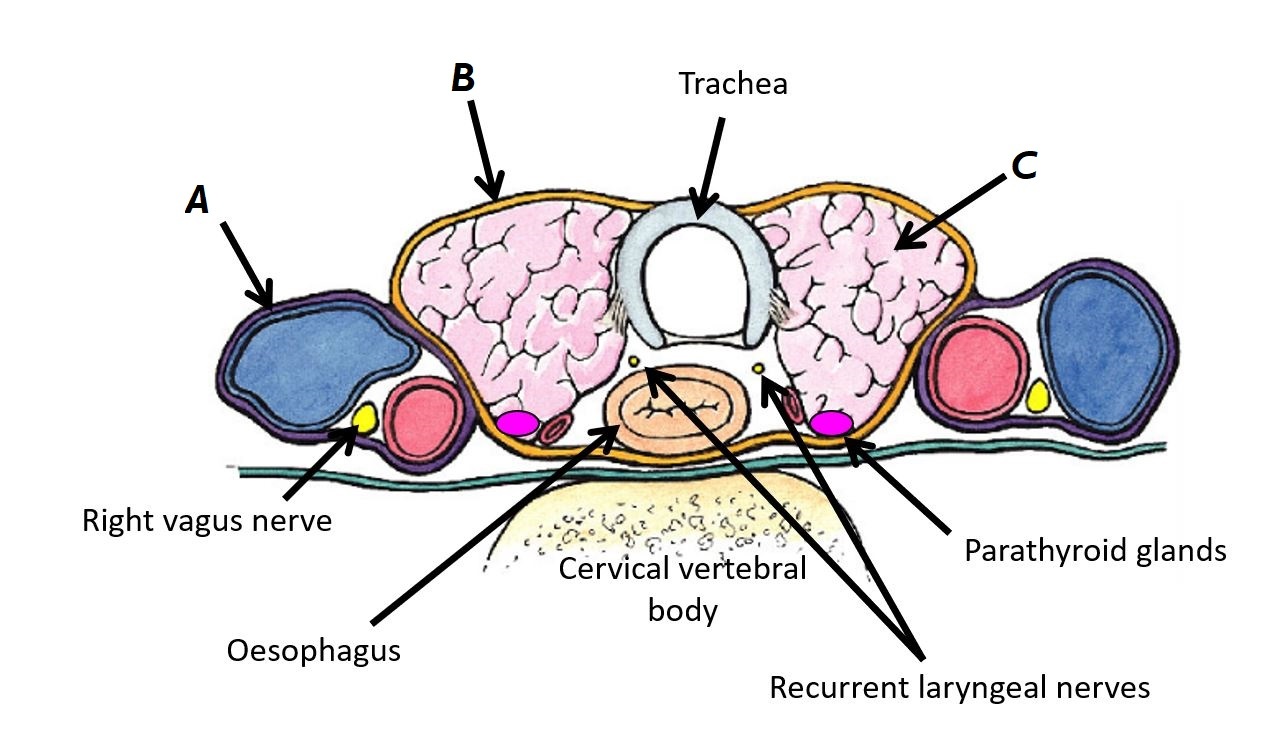

Name structures A, B and C

A - Right vagus nerve

B - Recurrent laryngeal nerves

C - Parathyroid gland